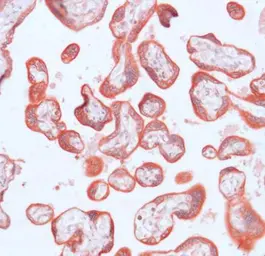

MMP23 antibody (ready-to-use)

Cat. No. GTX15479

ApplicationsIHC-P

ReactivityHuman